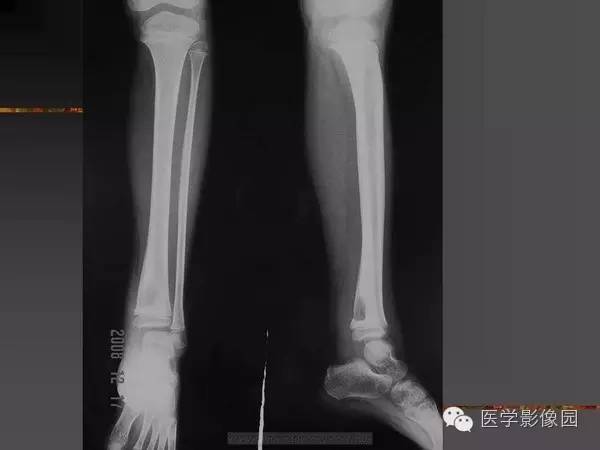

【病例】浆细胞性骨髓炎1例X线及CT影像表现